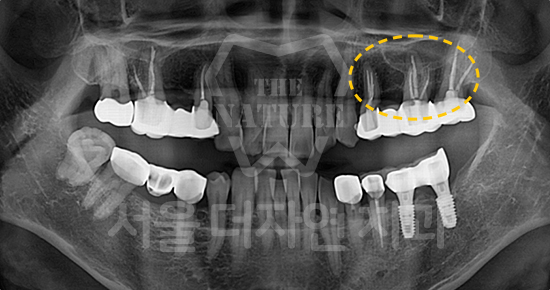

#상악 골이식

-

BEFORE: 2021.11.02

AFTER: 2022.01.19